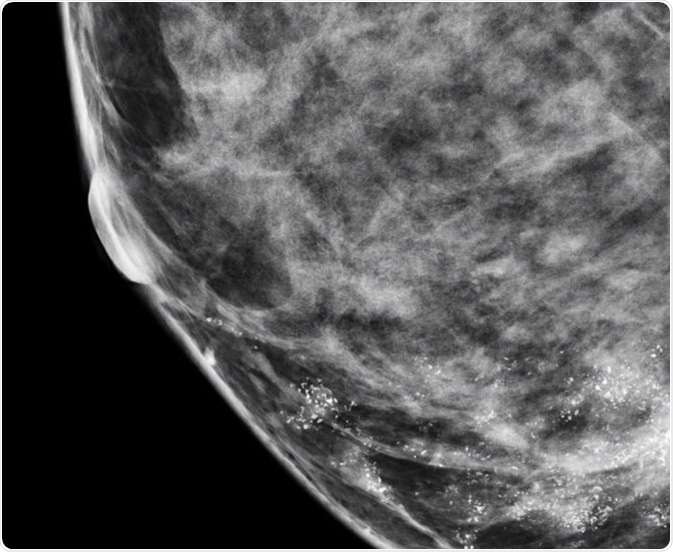

Microcalcifications are actually calcium deposits and are seen as tiny, white dots on a mammogram. They are much less common and are mostly a result of mutations in the breast tissue, though they can be caused by other factors. The appearance of microcalcifications is widely used in the detection of breast cancer at an early stage and can lead to better outcomes.

Nearly 50% of non-palpable cancers in the breast are detected only by the presence of microcalcifications on a mammogram, and approximately 93% of people with ductal carcinoma in situ (DCIS) also present with microcalcifications. Microcalcifications in the breast are very common in women and some studies have observed significant variations in the elemental composition of benign and malignant calcifications.

In general, when the distribution of microcalcifications is diffuse or bilateral, when they have a round and/or punctuate shape, or when they are scattered in the breast tissue, the condition is usually benign. On the other hand, if microcalcifications have a linear or branching pattern with irregular borders, or if they have variable density, or when they are distributed in a haphazard or segmental way, there is a high probability that it is ductal carcinoma in situ or malignant cancer.